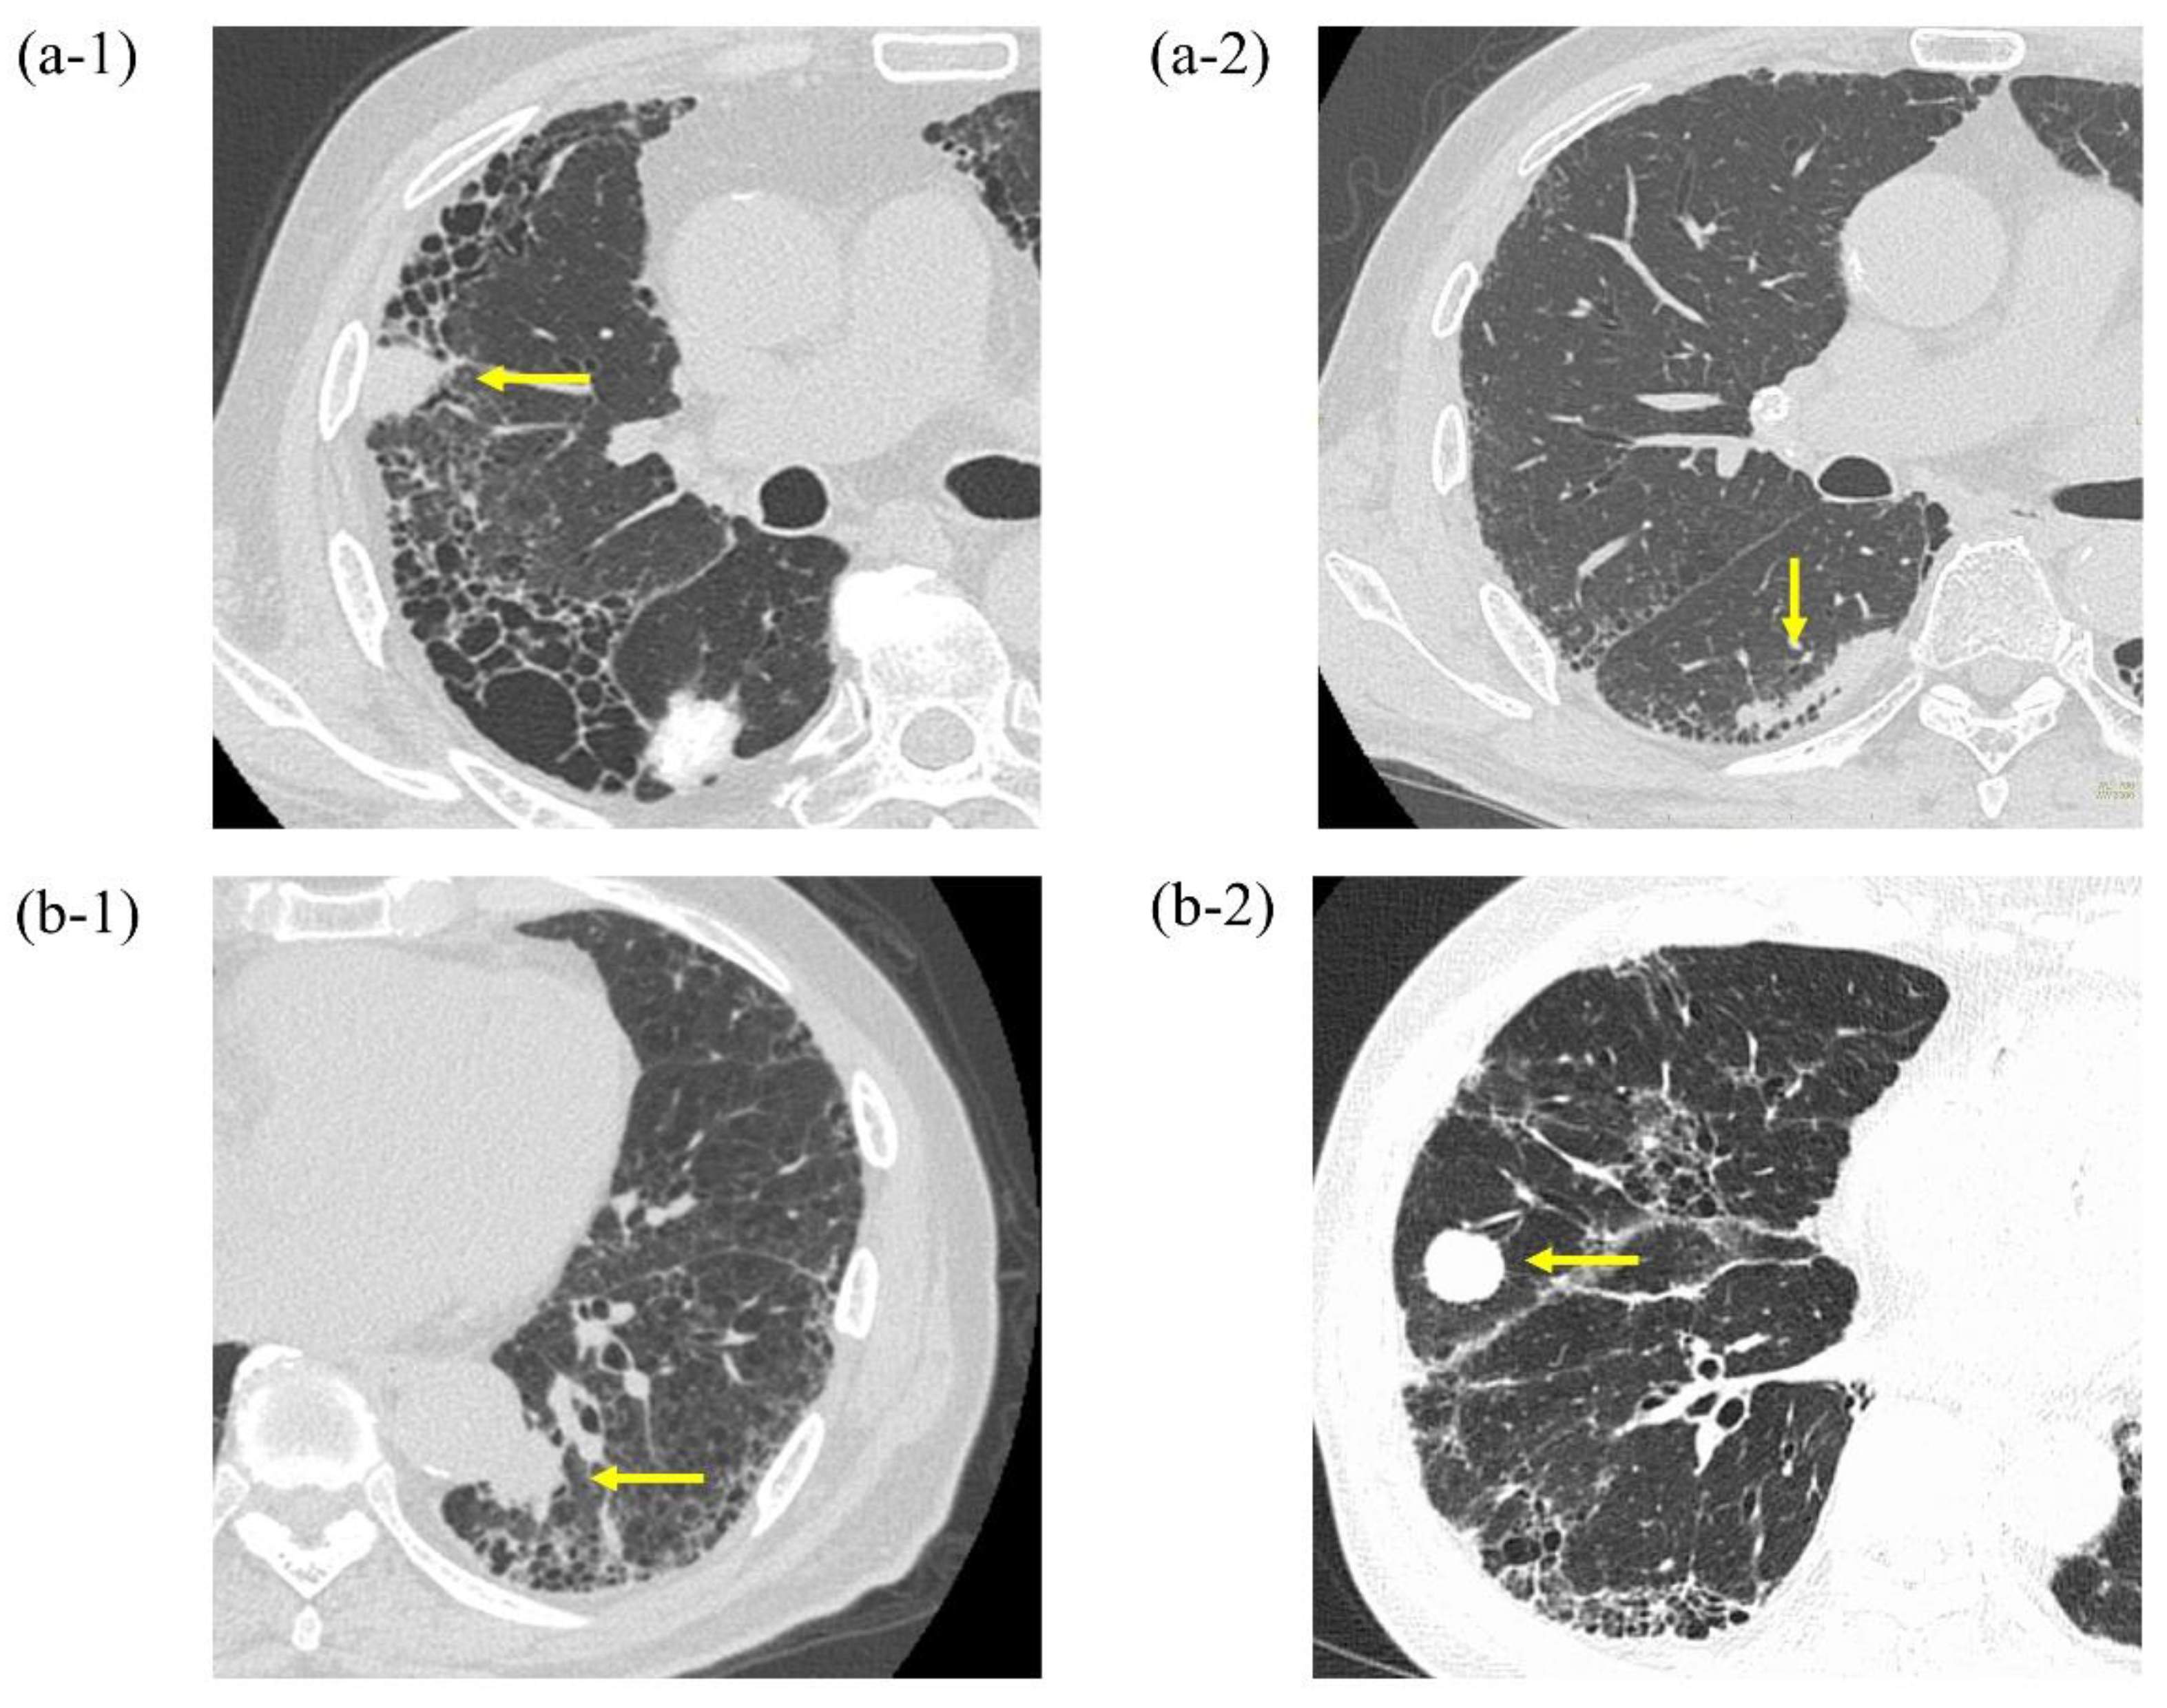

Endobronchial Ultrasonography with a Guide Sheath Transbronchial Biopsy for Diagnosing Peripheral Pulmonary Lesions within or near Fibrotic Lesions in Patients with Interstitial Lung Disease

3.2. Diagnostic Yields by Probe Location and Disease Type between PPLs within or near Fibrotic Lesions and Those Distant from Fibrotic Lesions